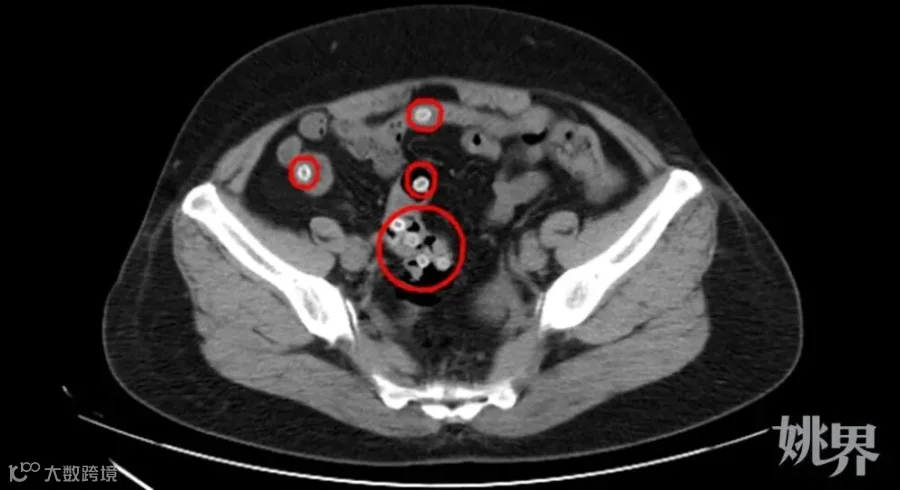

CT影像显示,患者肠道内有不少杨梅核滞留

CT影像显示,王阿姨的肠内存在多处类圆形高密度影,密密麻麻的圆圆小白点正是滞留在肠道内的杨梅核,这是导致患者腹痛不止的罪魁祸首。